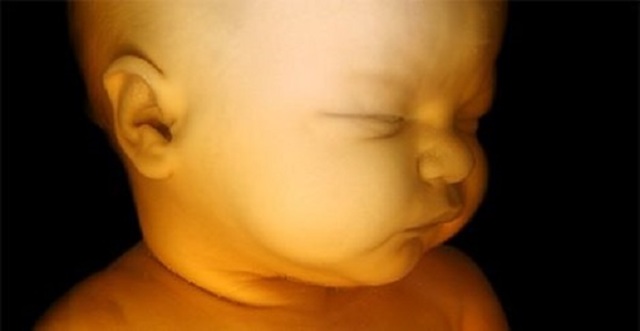

• Semana 11- 14

Semana 11- 14

Los párpados del feto se cierran y no se vuelven a abrir casi hasta el final de la gestación. La cara del feto ya se encuentra formada aunque su cabeza sigue siendo muy grande sin proporción con el resto del cuerpo. Las extremidades son largas y delgadas. En estas semanas se desarrollan las uñas de los dedos. El hígado ya produce glóbulos rojos y sus manos ya pueden formar puños.